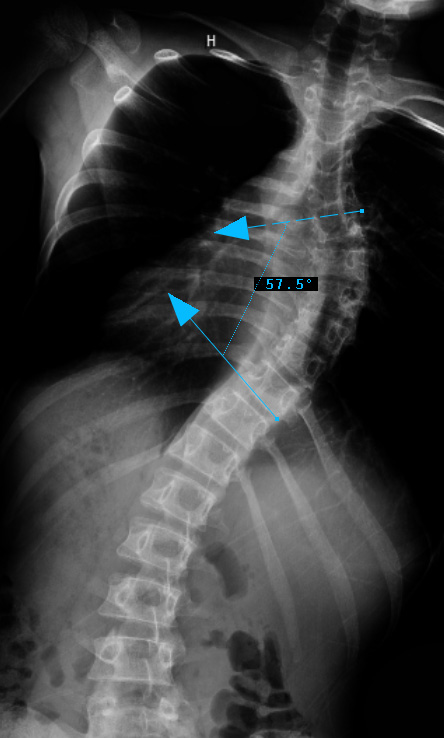

Preop RIGHT Bend

thoracic curve non-structural, main thoracic curve major, Lumbar curves non-structural.

Lenke Type III describes a double major curve pattern. The main thoracic curve is considered the major curve as the greatest coronal plane deformity is present between T2 and the T11-12 disc. In Lenke Type III curves, the thoracolumbar/ lumbar spine is also considered structural. By definition, the thoracolumbar/ lumbar spine is structural if the deformity is greater than 25 degrees on side-bending radiographs or if the T10-L2 kyphosis is greater than 20 degrees in the sagittal plane. All lumbar and sagittal modifiers remain applicable in Lenke Type III curves. In general, both the MT and ThL/L curves are treated with instrumentation and fusion. The upper instrumented vertebra is between T2 to T4 depending on shoulder position and the lowest instrumented vertebra is either L3 or L4. The LIV should have near-neutral rotation, be at least one disc level below the apex of the lumbar curve and the disc below the LIV should be parallel or wedged open opposite to the side of the apex of the curve.